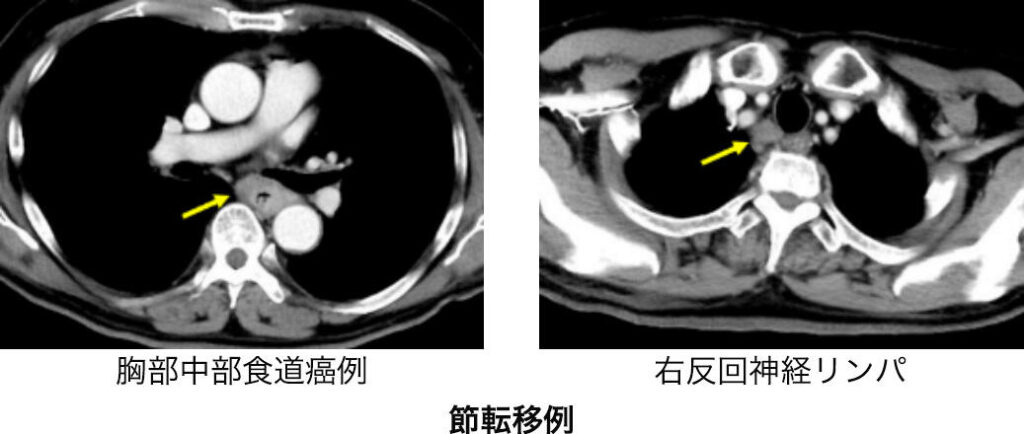

CT(コンピューター断層撮影)で頸部から腹部までの撮影を行います。造影剤を併用することで血流のコントラストが鮮明となり診断能が高まります。食道癌の壁深達度がどうであるか、他臓器(気管、大動脈など)への浸潤はないか、食道周囲や遠くのリンパ節に転移がないか、肺や肝臓など他臓器に転移がないか、そして手術を検討するに解剖学的特徴について調べます。